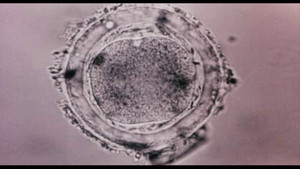

In The Womb